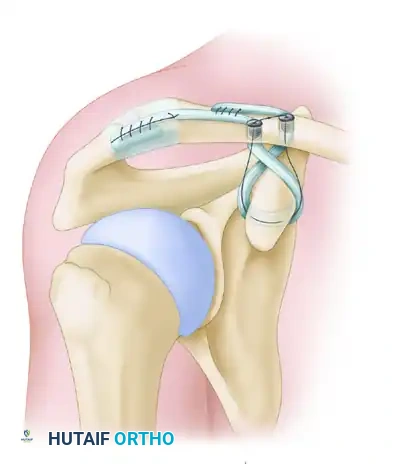

7. Reduction and Interference Screw Fixation

- Reduction: Elevate the arm and apply a superiorly directed force to the elbow to elevate the scapulohumeral complex. Simultaneously, apply a gentle downward force on the clavicle.

- Surgical Pearl: Slightly overreduce the acromioclavicular joint by 2 to 3 mm, as minor settling of the graft is expected postoperatively.

- Fixation: While maintaining the reduction, secure the graft limbs within the clavicular tunnels using soft tissue interference screws (typically 5.5 mm or 6.25 mm PEEK or biocomposite screws).

- Insert the first screw into the posterior (conoid) tunnel, bringing the whipstitch sutures up through the cannulation of the screw.

Secure the graft with a soft tissue interference screw in the posterior tunnel. The sutures are brought through the cannulated screw to allow for secondary fixation.

- Assess the reduction and screw placement. Once confirmed, place the second interference screw into the anterior (trapezoid) tunnel.

- Secondary Fixation: Tie the high-strength sutures from the medial and lateral limbs together over the bony bridge between the two tunnels to provide a secondary node of fixation and back up the interference screws.

Interference screw fixation of the graft to the clavicle, followed by tying the high-strength sutures over the intervening bone bridge for augmented construct security.

8. Acromioclavicular (AC) Ligament Reconstruction

To address anteroposterior instability at the AC joint itself, the residual tail of the graft is utilized.

* Route the remaining lateral limb of the tendon graft over the AC joint.

* Secure it to the acromion using suture anchors or by passing it through drill holes in the acromion, effectively reconstructing the superior AC capsular ligaments.

Final placement of grafts. The residual lateral limb is routed and sutured to the acromion, completing the acromioclavicular ligament reconstruction and providing horizontal stability.